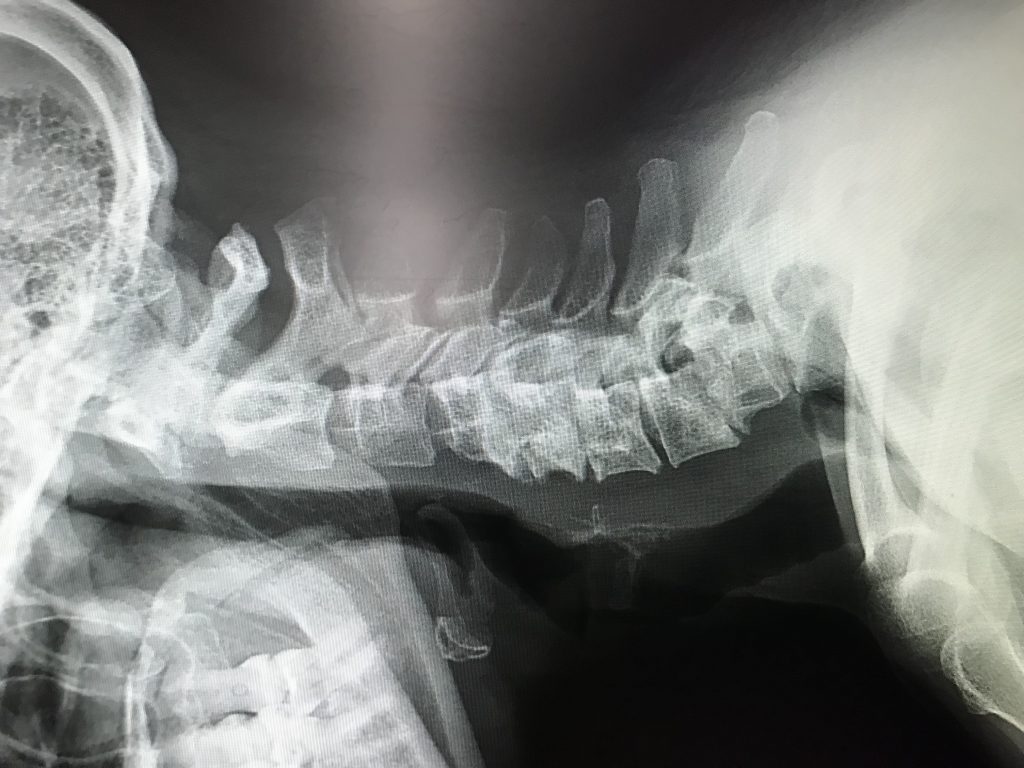

In my cervical spine I had 4 levels of compressed nerves, C-4-T1, spondylolisthesis, spondylolysis, spinal stenosis and severe degenerative disc disease. I was only 42 years old. I saw 2 local surgeons in Albany who both said surgery was imminent. However, one said he would go through the front of my neck (anterior), while the other said he did not think an anterior cervical fusion would hold because of the severe structural compromise of my neck. He said he would go in through the back (a very painful recovery with longer healing time).

Dr. Farmer certainly agreed that I had a big problem. He said my neck on an MRI looked like a 90-year-old gymnast. He knew I was mentally not ready for surgery,(I was too scared) but told me when my arm and hand really started to become a problem, (and I would know) to get to him quickly. After 5 years of meds, exercises, and a lifestyle change, the time came. During a walk my shoulder blade down through my fingers felt like I was being electrocuted. My arm and fingers were moving on their own, but the pain was excruciating! I visited the ER in hopes of some relief. They did an MRI and called Dr. Farmer. I went to see him on a Friday and he had me in surgery on Tuesday.